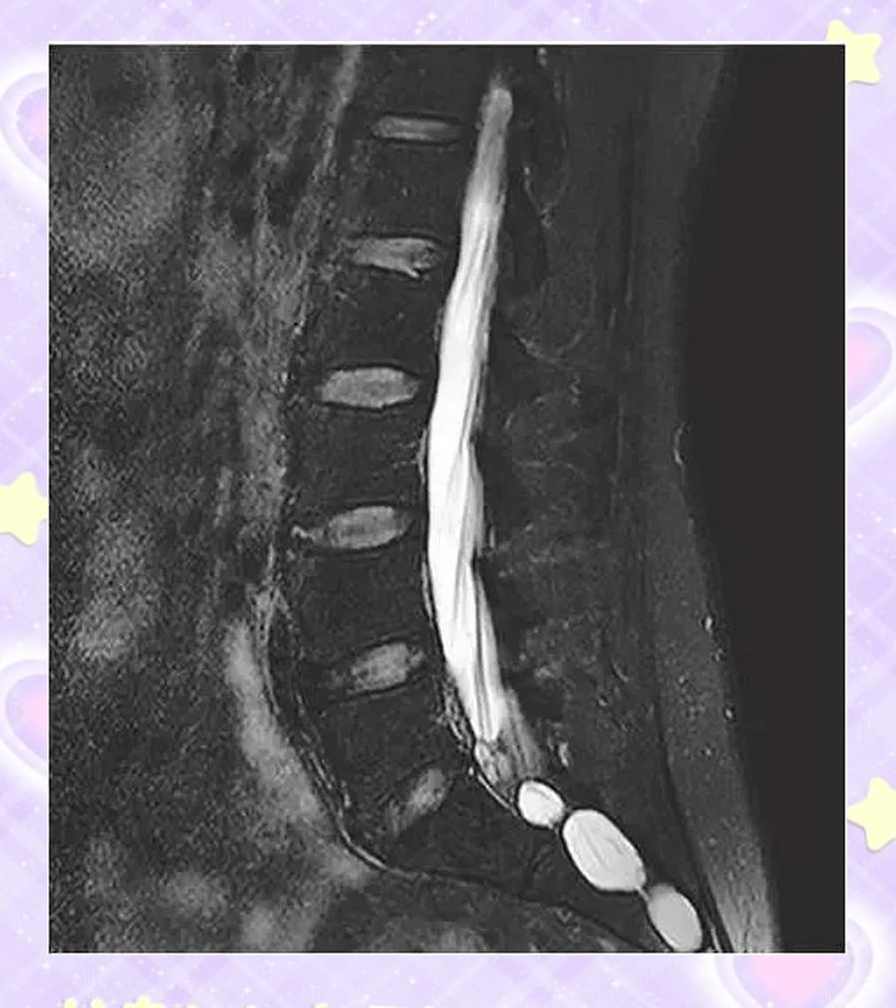

骶管囊肿如何治疗?

腰骶管囊肿的治疗需根据患者症状囊肿大小及位置等因素制定个性化方案,主要分为观察手术治疗和其他治疗三类一观察治疗适用于无症状或症状轻微的患者医生会建议定期进行影像学检查如MRI或CT,监测囊肿大小及症状变化观察期间,患...